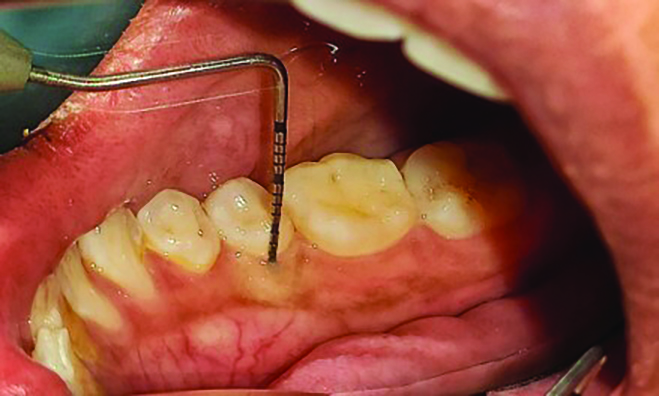

Fig 1 through Fig 3. Measurements of lingual attached gingiva: Fig 1 = identifying the MGJ.

Figure 1

Fig 2 = sulcus depth measurement.

Figure 2

The MGJ was delineated by the visual method and the roll method following clinical examination in dental chairs appropriately equipped. Visual assessment relies on identifying the color difference between the gingiva and alveolar mucosa. The mucosa beyond the MGJ typically appears darker red compared to the AG, helping to demarcate the MGJ. The rolling probe method entails pushing the neighboring alveolar mucosa coronally with the blunt end of a probe. It is a functional assessment method that aids in determining the boundary between gingiva and movable mucosa.10 The probing sulcus depth was subtracted from the measured KG width at the mid-lingual aspect of each tooth to determine the width of AG, and all fractional measurements were rounded off to the nearest whole number of millimeters (Figure 1 through Figure 3).